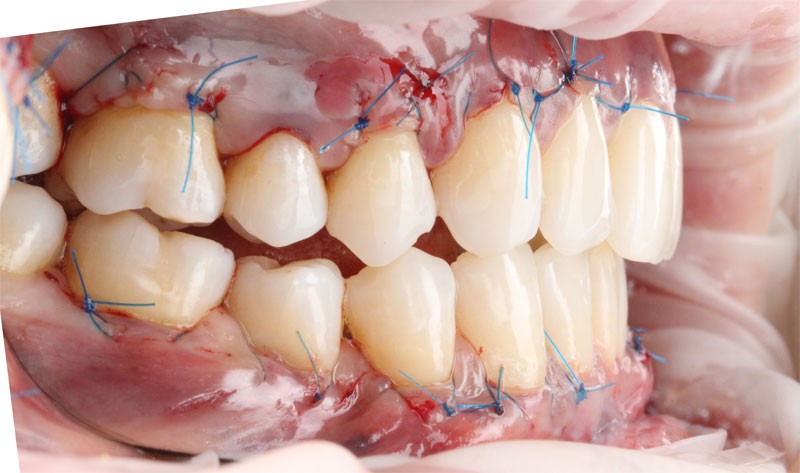

- Лоскутная операция⁚ этот метод заключается в отслаивании десневого лоскута, удалении подлежащего зубного камня и перемещении лоскута на место, закрывая оголенные корни зубов.

Выбор оптимального метода лечения осуществляется врачом-пародонтологом после тщательного обследования и оценки состояния полости рта.